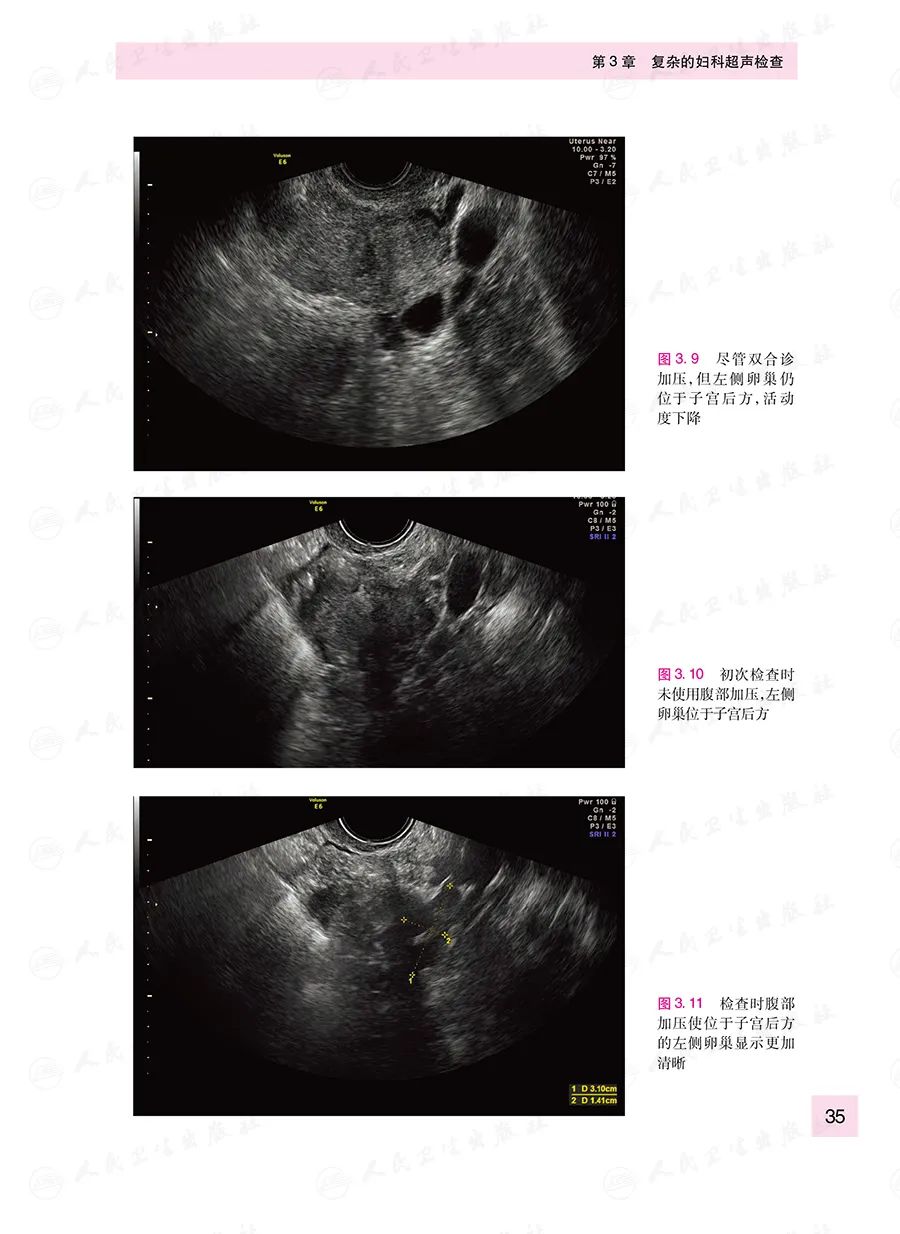

本书原著由英国妇科超声专家编写,定位于从事妇科超声工作的低年资医生,从妇科超声实际工作中仪器调节、操作手法、图像优化等基础知识讲起,进而对常见妇科疾病的超声诊断与鉴别诊断进行了归纳总结。全书强调实用性,以帮助读者了解日常工作中容易被忽略的细节问题,有助于读者快速掌握并提升临床诊断技能。本书各章节涵盖的主题全面,包括设备的熟悉,经阴道超声的操作原则,棘手的子宫和卵巢,与ART相关的超声评估等。书中讨论了二维和三维超声的应用,并阐述了如何优化图像质量,如何在具有挑战性的评估中获得有用的临床信息。大量的图像可以帮助读者熟悉正常的解剖结构和常见疾病。章节中的总结部分和基于疾病的病例展示也为评估病情和病变提供了有价值的参考。